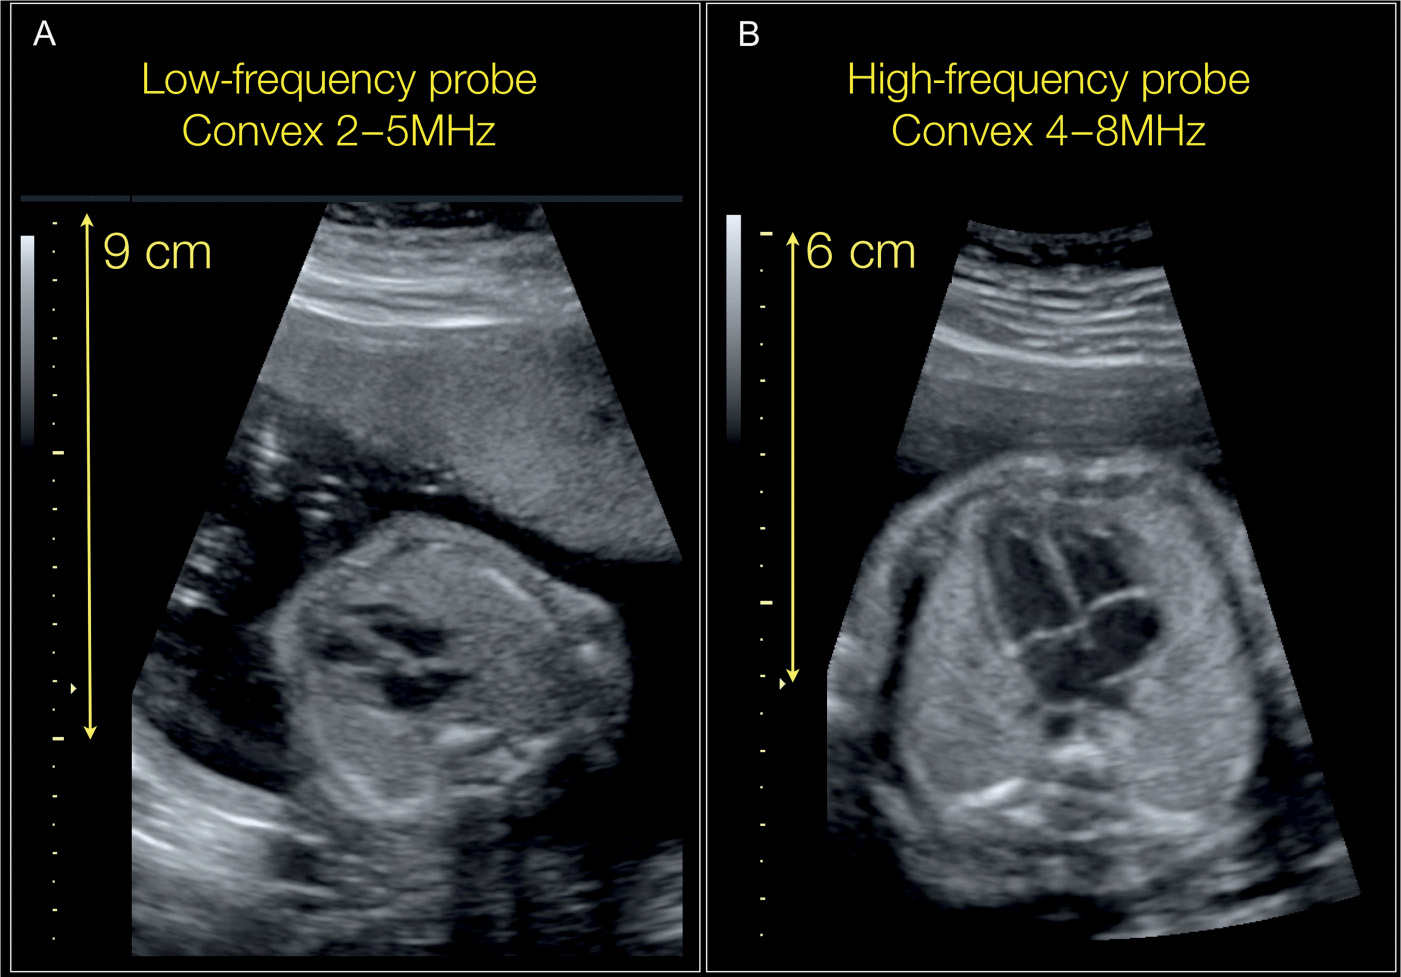

( A ) Lowfrequency transducer with long spatial pulse length and low What Is Low Frequency Ultrasound  The low‐frequency low‐intensity non‐contact ultrasound for a venous leg wound ulcers had a significantly lower non‐healed. Ultrasound frequencies in diagnostic radiology range from 2 mhz to approximately 15 mhz. Ultrasound as a therapeutic agent in chronic wound healing has been studied extensively. Cavitation, frequency, intensity, and duty cycle. Higher ultrasound frequencies have shorter. In fact, high power industrial applications of.. What Is Low Frequency Ultrasound.